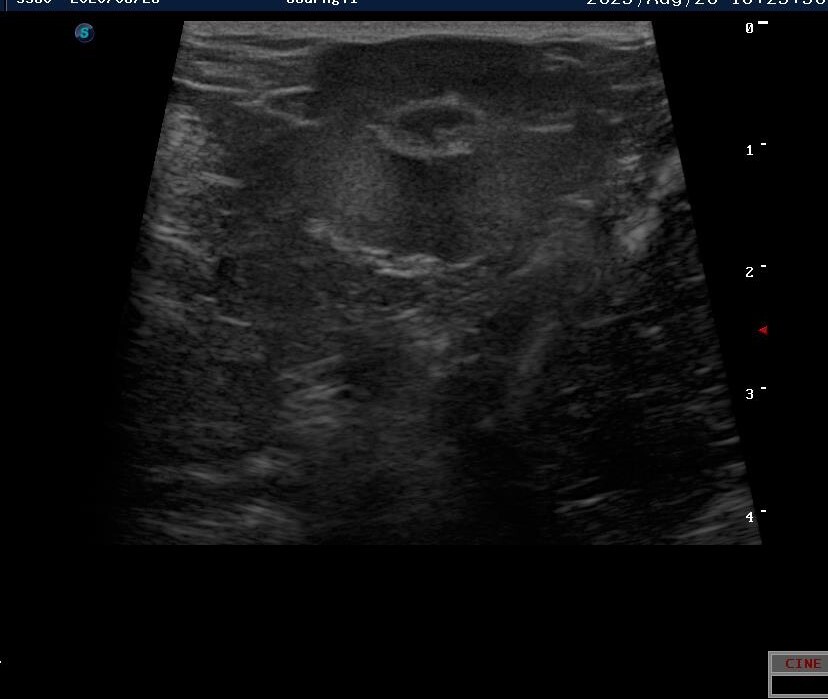

방사선 및 복부 초음파

이 아이의 경우 육안으로도 확연하게 확인이 가능할 정도로 서혜부쪽의 배가 볼록하게 나와있었습니다.

정확한 상태를 파악하기 위해서 엑스레이와 복부 초음파 검사를 하였습니다.

서혜부 탈장이 확인 되었고 수술을 진행하기로 결정하였습니다. 아이는 며칠 동안 입원하여 안정을 취하기로 하였습니다.